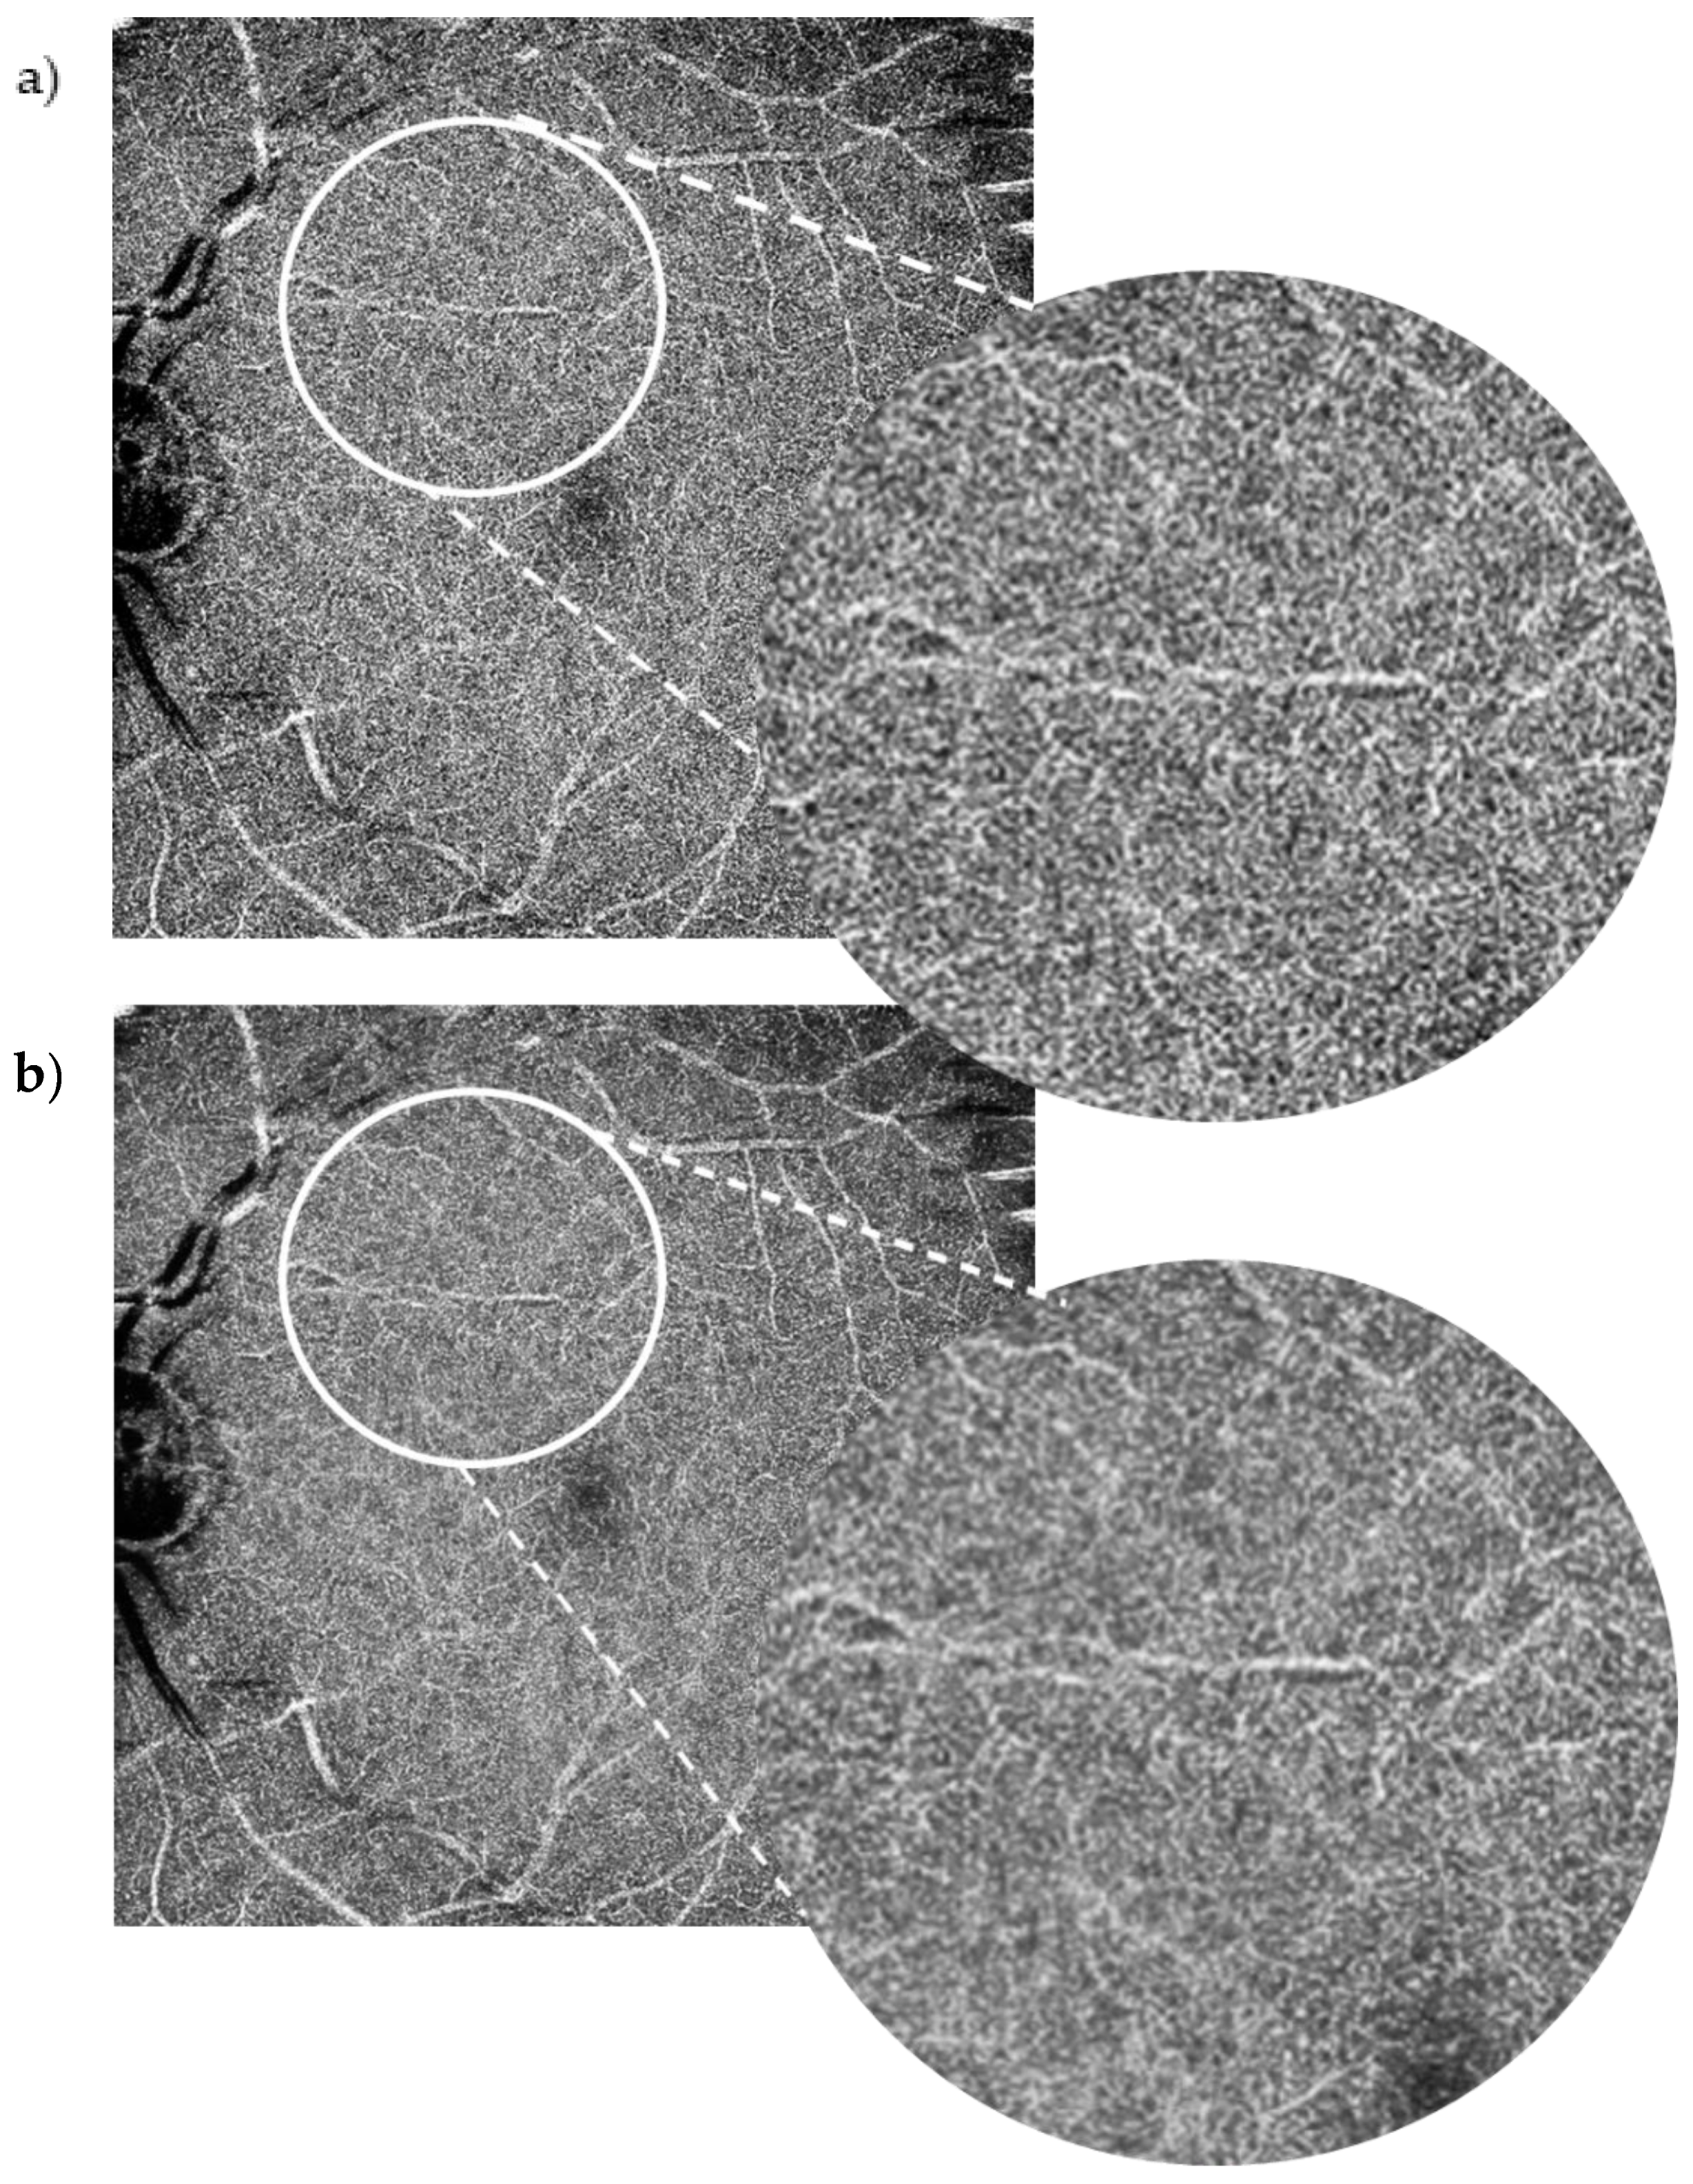

Each patient had wide-field (10 × 10 mm) macula OCT-A scans on the Canon Xephilio OCT-A1 machine with 10-layer automated segmentation and a refresh rate of 70,000 A-scans/second. Depth of field of view was set to 10 × 10 mm with an axial sampling density of 464 × 464 pixels. The number of repetitions was set at 2. The position of the field investigated was centred on the foveal region. En face OCT-As were segmented automatically using built-in software that defines each different retinal layer. The enhanced artificial image was automatically created by selecting the “denoise” button after image acquisition to initiate the algorithm, which completed processing in approximately 2 s. The same technician captured the scans of each patient in this way. All OCT-A images were qualitatively examined for severe motion or shadow artefacts. Figure 1 and Figure 2 demonstrate denoised images created this way along with their corresponding baseline images.

The SCP layer was analysed before and after denoising in 49 scans. Comparison between the original and the denoised image was documented using a proforma as seen in the Appendix A, Figure A2. The denoised DCP of the same 49 scans was similarly analysed and compared with the original image. Please see Figure 2 for an example of an original OCT-A scan of the SCP compared with its denoised equivalent. Please see Figure 3 for an example of an original OCT-A scan of the DCP compared with its denoised equivalent.

Figure 2. 10 × 10 mm OCT-A scan of the deep capillary plexus. Baseline image (a) vs. denoised image (b). The positive impact of the denoise software on the Superficial Capillary Plexus (SCP) did not apply to the same extent to the Deep Capillary Plexus (DCP). Although the more clinically standard smaller field DCP scans were of higher quality, the widefield 10 × 10 mm images for this study showed shadowing from the SCP and relative loss of clarity.